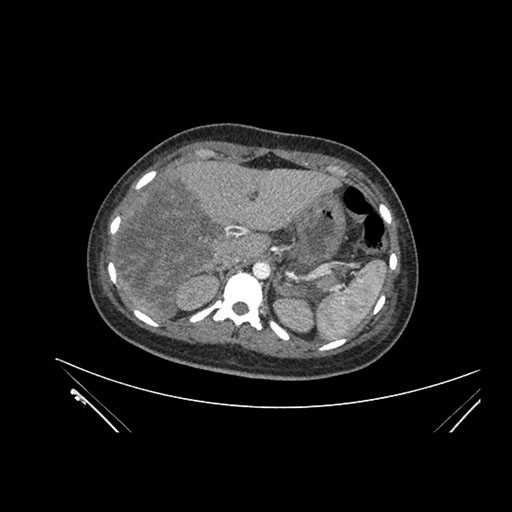

Imaging Analysis

Look through the patient's CT scan to identify any areas of concern for the necessary procedure.

Coronal Arterial

Based on initial findings, which issue(s) would you be most concerned about?